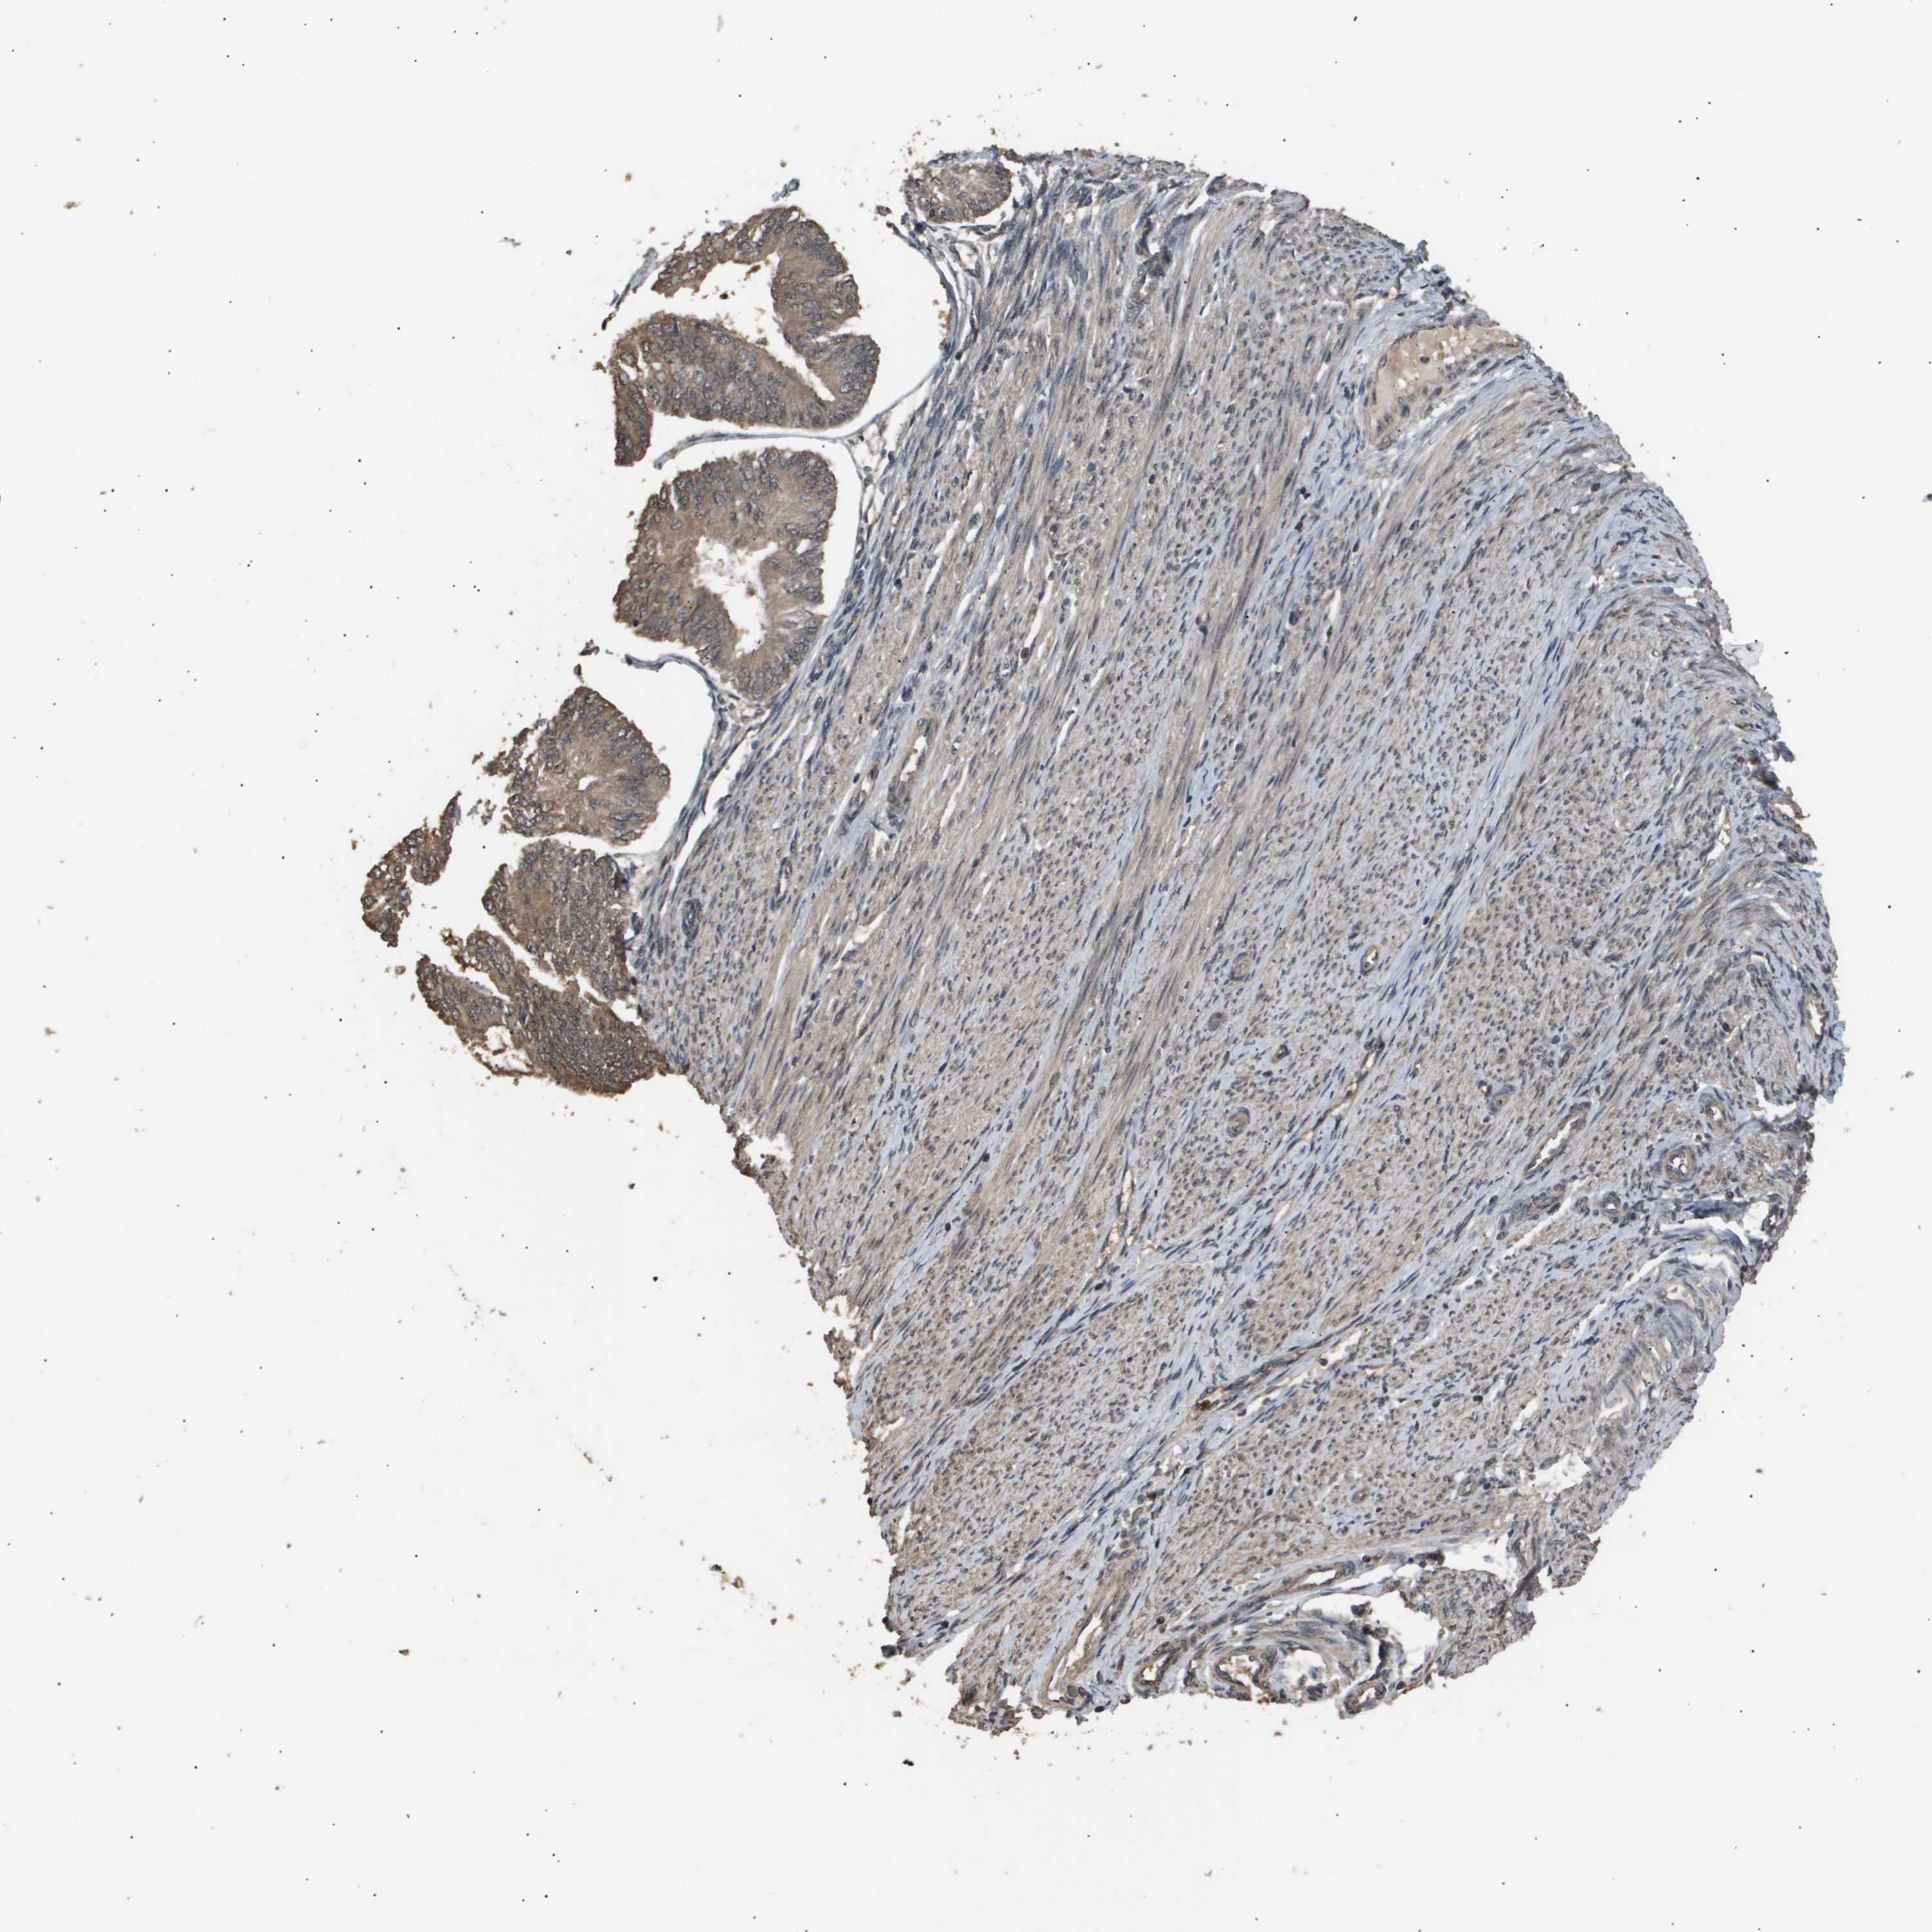

ENDOMETRIAL CANCER - Protein expressioni

A mouse-over function shows sample information and annotation data. Click on an image to view it in a full screen mode. Samples can be filtered based on level of antibody staining by selecting one or several of the following categories: high, medium, low and not detected. The assay and annotation is described here.

Note that samples used for immunohistochemistry by the Human Protein Atlas do not correspond to samples in the TCGA dataset.

Antibody stainingi

Antibody staining in the annotated cell types in the current human tissue is reported as not detected, low, medium, or high, based on conventional immunohistochemistry profiling in selected tissues. This score is based on the combination of the staining intensity and fraction of stained cells.

Each image is clickable and will lead to virtual microscopy that enables deeper exploration of all samples and also displays staining intensity scores, fraction scores and subcellular localization as well as patient and tissue information for each sample.

Antibody CAB016136

Antibody CAB017773

Staining

High

Medium

Low

Not detected

Intensity

Strong

Moderate

Weak

Negative

Quantity

>75%

75%-25%

<25%

None

Location

Nuclear

Cytoplasmic/membranous

Cytoplasmic/membranous,nuclear

Adenocarcinoma, NOS